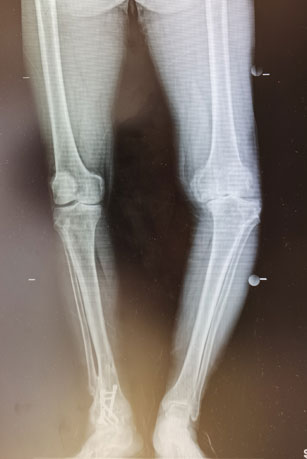

患者是一位老年男性,因年轻时外伤导致左膝创伤性关节炎,常年从事体力劳动,随着年龄的增长,膝关节畸形,疼痛越来越重,已经严重影响了生活质量。8年前,我院骨科主任医师王兴龙曾为这位患者行重度踝关节炎胫距关节融合术,术后患者非常满意,此次再次来到了王兴龙的门诊。

王兴龙为患者进行了详细查体,完善了相关检查,发现患者膝关节内翻畸形达25度,并伴有近20度的屈曲挛缩畸形,手术难度极大。手术可能需要特殊关节假体,但此类假体费用非常昂贵。为了以最经济的方法获得同样的疗效,王兴龙通过术前仔细测量、规划,决定为患者应用普通关节假体进行手术。术中,患者膝关节异常僵硬,软组织松解、平衡困难,截骨后胫骨侧伴有较大的骨缺损。由于术前准备充分,通过袖套样松解、拉花技术、胫骨平台缩小、应用水泥螺钉技术,手术难点被一一攻克。在麻醉科、手术室和关节团队的密切配合下,手术顺利完成。术后,我院康复医学科为患者进行个性化的康复治疗,术后第五天,患者康复出院。